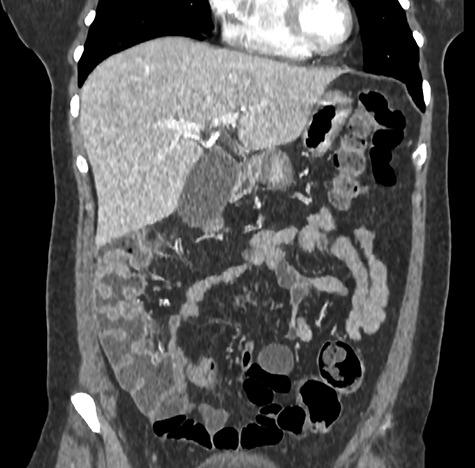

Herniation through the foramen of Winslow is rare, with a non-specific clinical presentation and his diagnosis may be difficult. A 44-year-old female was admitted with an acute epigastric abdominal pain. A computed tomography showed an internal hernia of the colon in the lesser sac. Laparoscopic reduction of the herniated contents and the fixation of the ascending colon with several non-absorbable sutures were performed. Twenty months after surgery, the patient has not experienced any recurrence. Computed tomography helps practitioners to the preoperative diagnosis of herniation through the foramen of Winslow, to the viability of the herniated contents and presence of occlusion. In case of herniation through the foramen of Winslow favored by a mobile ascending colon with a misapposition of the right Told fascia, the fixation of the colon with a non-absorbable suture was safe and may prevent the risk of recurrent internal hernia and colonic volvulus.

通过网膜孔的疝出很少见,临床表现不具特异性,其诊断可能困难。一名44岁女性因急性上腹部腹痛入院。计算机断层扫描显示小网膜囊内有结肠内疝。进行了腹腔镜下疝内容物还纳及用数根不可吸收缝线固定升结肠。术后20个月,患者未出现任何复发。计算机断层扫描有助于医生对通过网膜孔的疝出进行术前诊断,判断疝内容物的活力及有无梗阻。对于因活动度大的升结肠伴右侧Toldt筋膜错位而导致的通过网膜孔的疝出,用不可吸收缝线固定结肠是安全的,且可预防复发性内疝和结肠扭转的风险。